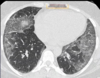

11

Hipertensão pulmonar

Relação artéria-brônquio